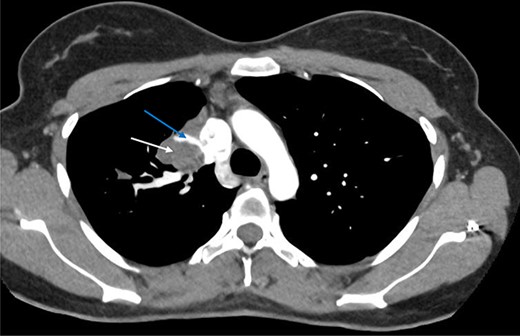

Computed tomography (CT) scans demonstrated a well-demarcated right-sided 5.5 × 2.6 cm paramediastinal solid mass, with associated atelectasis of the RUL (Figs 1 and 2). Traversing this segment, a large venous tributary of the azygous vein was identified (Fig. 2).

Axial arterial phase CT scan demonstrating pulmonary sequestration (bottom arrow). A large venous branch draining into the azygous vein can be identified (top arrow).